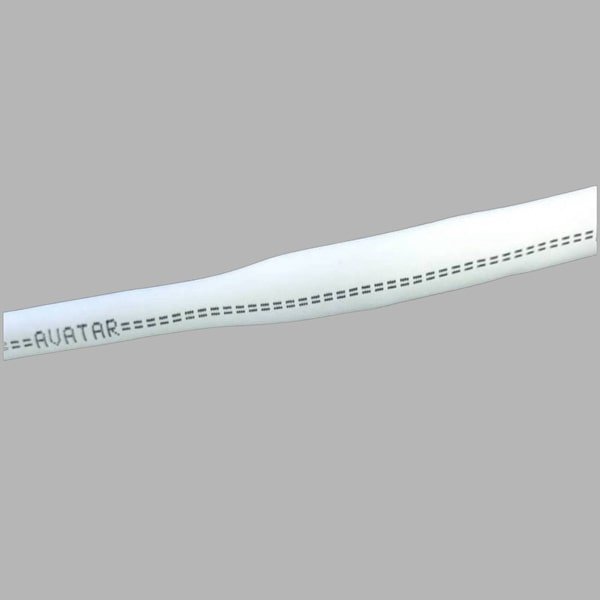

AVATAR® PTFE Vascular Grafts are made entirely from PTFE. The AVATAR® graft does not have an external wrap but instead has an open pore structure averaging 20 microns internodal distance, encouraging tissue ingrowth and making it soft and easy to suture.

AVATAR® PTFE Vascular Grafts are made entirely from PTFE. The AVATAR® graft does not have an external wrap but instead has an open pore structure averaging 20 microns internodal distance, encouraging tissue ingrowth and making it soft and easy to suture.

Arterio-Venous Grafts – Standard

| 1 | 20cm | 5mm | PVGRG0520 |

| 2 | 20cm | 6mm | PVGRG0620 |

| 3 | 45cm | 5mm | PVGRG0545 |

| 4 | 45cm | 6mm | PVGRG0645 |

AVATAR® PTFE Vascular Grafts are made entirely from PTFE. The AVATAR® graft does not have an external wrap but instead has an open pore structure averaging 20 microns internodal distance, encouraging tissue ingrowth and making it soft and easy to suture. Helix grafts incorporate an external PTFE spiral support for use in applications where kink or crush resistance is required. Tapered and step tapered grafts can allow for better management of blood flow. All AVATAR® PTFE Vascular Grafts come sterile in dual barrier tray-within-tray packaging.